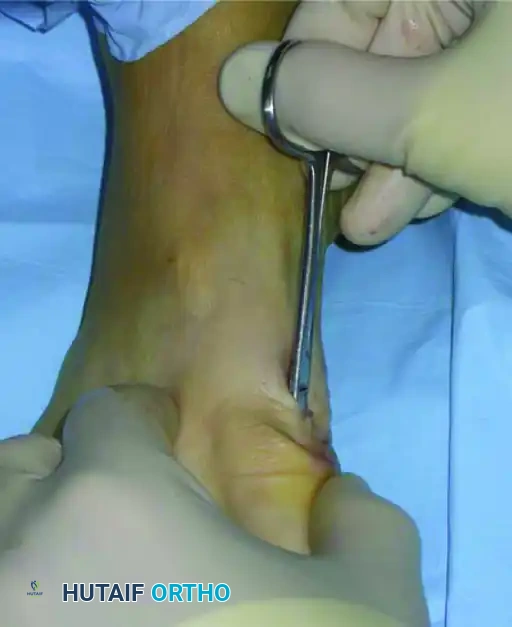

Because the capital fragment has been translated laterally, the medial skin and soft tissues may become tethered or invaginated around the K-wire insertion site.

- Using a small hemostat or tenotomy scissors, gently release the soft tissue at the level of the skin incision to prevent skin necrosis and alleviate tension.

FIGURE 81-38A Percutaneous distal metatarsal osteotomy. The soft tissue is released at the level of the skin incision.